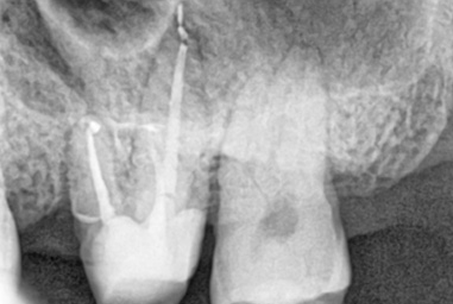

위 사진들은 현직 치과의사들이

저희 웃는얼굴 치과에서 치료 받은 실제 사례들입니다.

비 전문가 눈에는 그냥 흔한 엑스레이 사진일 뿐이겠지만

치과의사들이라면 알아챕니다.

저 치료가 얼마나 난이도 있는 치료였는지,

얼마나 정성이 들어갔는지를 말이지요.

크라운과 기존의 신경관 충전물질을 제거 후

다시 신경치료를 진행하는 술식입니다.

일반적인 신경치료보다 어렵고 성공률이 떨어지기 때문에

전문적인 치료가 필요합니다.

특히 신경관이 막혀있거나 신경관에 POST가 박혀있는 경우

재신경 치료의 난이도는

매우 높아지며, 많은 환자분들이

재신경치료가 불가능하다며 발치를 권유 받습니다.

하지만 웃는얼굴치과에서는 특수 초음파 기구로 막힌

신경관을 찾거나

신경관에 박혀있는 POST를 제거한 후

재신경치료를 하여

환자분들의 치아를 살려드리고 있습니다.